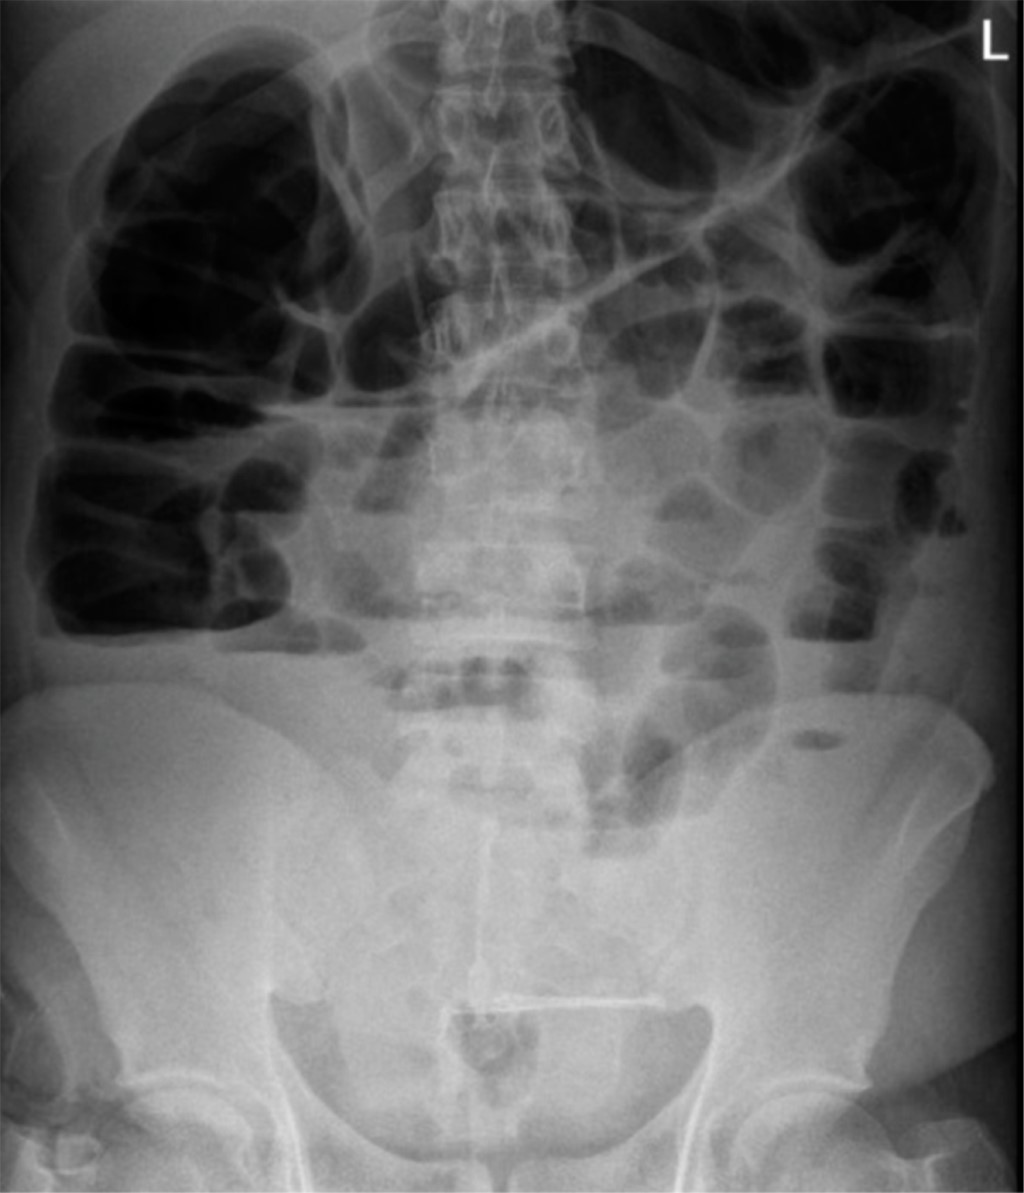

Introduction: rectal cancer can occur in young patients with no family history, so it is important to assess screening studies in the young population. Clinical case: 25-year-old male with no family history, goes to the emergency department due to a distal bowel obstruction with a history of 30 kg weight loss and diarrhea of six months' duration, imaging studies with an upper rectal lesion and secondary liver nodules. Discussion: results from studies worldwide support the benefits of changing the age of screening for colorectal cancer for patients of any age. The implementation of screening is intended to reduce mortality, but not incidence rates. Conclusions: it is necessary to take into account and assess the signs and symptoms of young patients who come to the consult with symptoms suggestive of a tumor and not wait for them to arrive at an emergency department with data of distal large intestine occlusion and think that cancer can be present also in young patients.

Figure 1